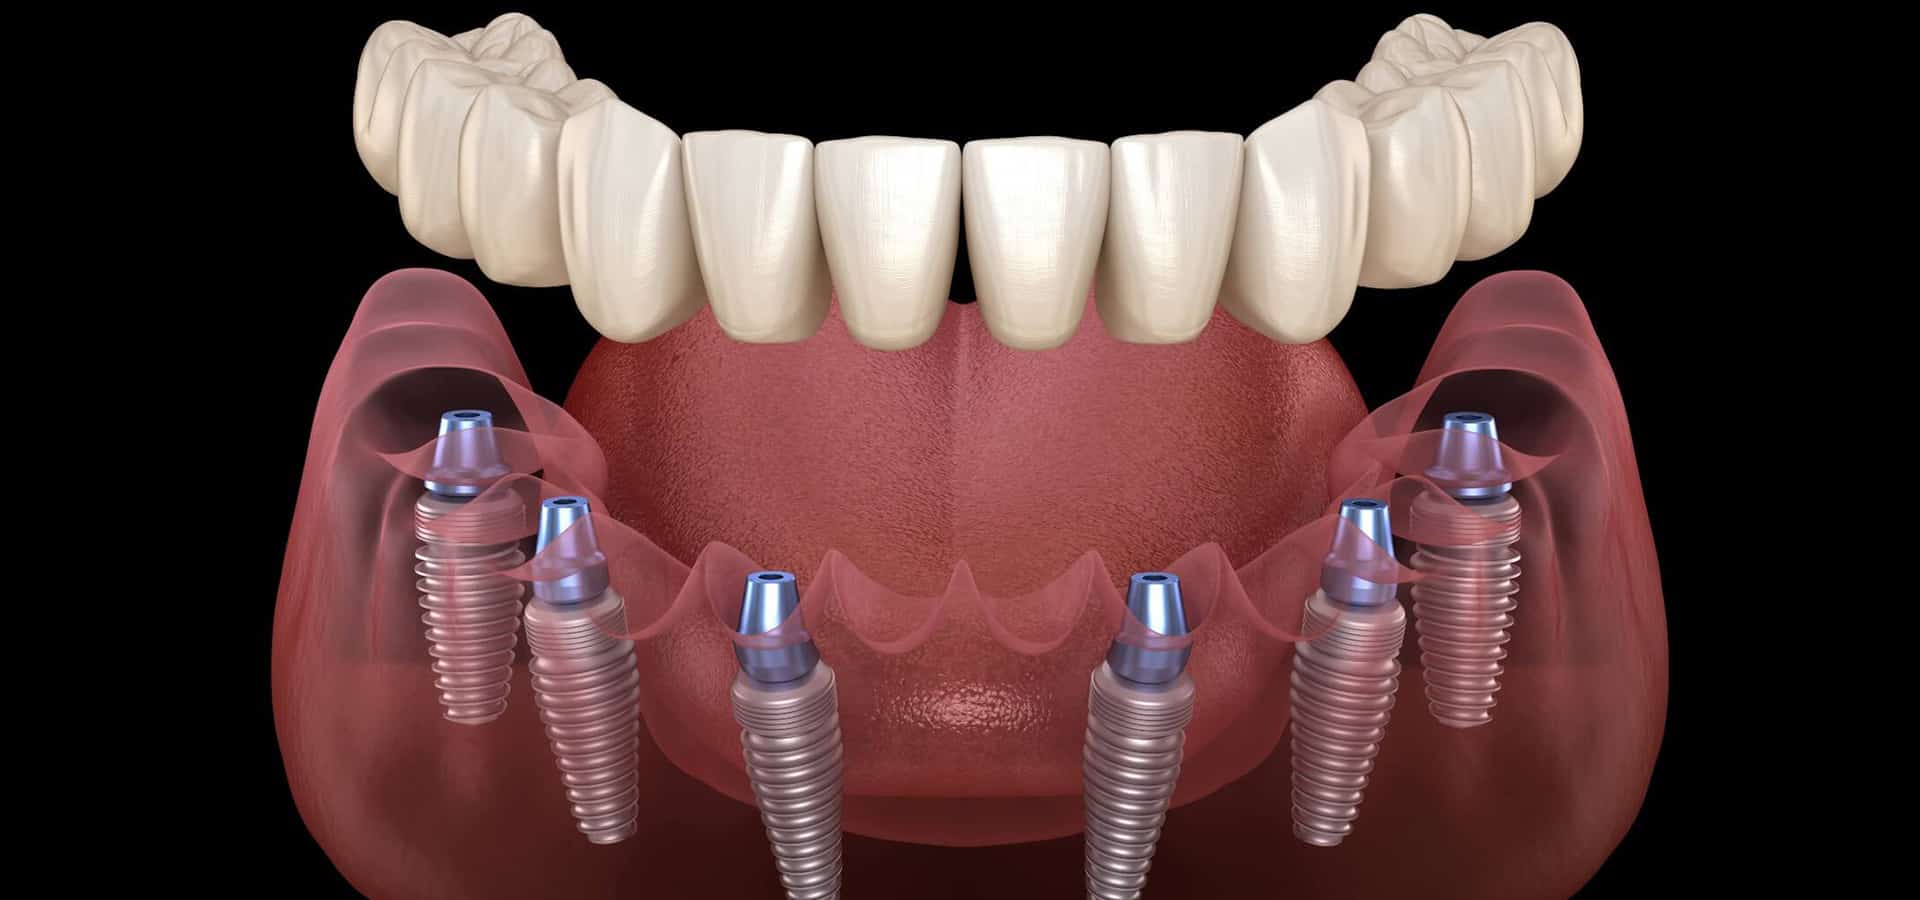

The terms "All-on-4" and "Teeth in a Day" describe a procedure where patients receive replacement teeth in a single day. Variations include "Teeth in an Hour," "Dental Implants in One Day," "Teeth In One Day," and "Teeth In One Visit." Despite different names, they all refer to a one-day implant treatment for restoring an entire arch of teeth.

The Teeth-in-a-Day treatment uses 4-6 dental implants to attach a new set of permanent replacement teeth minimally invasively. These implants are designed for immediate function and often eliminate the need for bone grafting. Ideal for denture wearers or those needing full upper and/or lower restorations, this procedure offers a beautiful smile in just one day.

Dr. Sista's approach involves only four specially placed implants, avoiding the need for bone grafts and sinus lifts. This results in fixed teeth that are not removable, reducing costs and healing times. Patients regain their smile and function faster and more reliably than with traditional methods.

How Does the Full-Arch Implant Procedure Work?

During the full-arch implant procedure, 4-6 appliances are surgically placed into the jawbone and gums. After allowing sufficient time for healing, the implant bridge is securely attached. This bridge closely resembles the appearance of natural teeth. Periodic evaluations are necessary to ensure the health of both the prosthetic and implants.